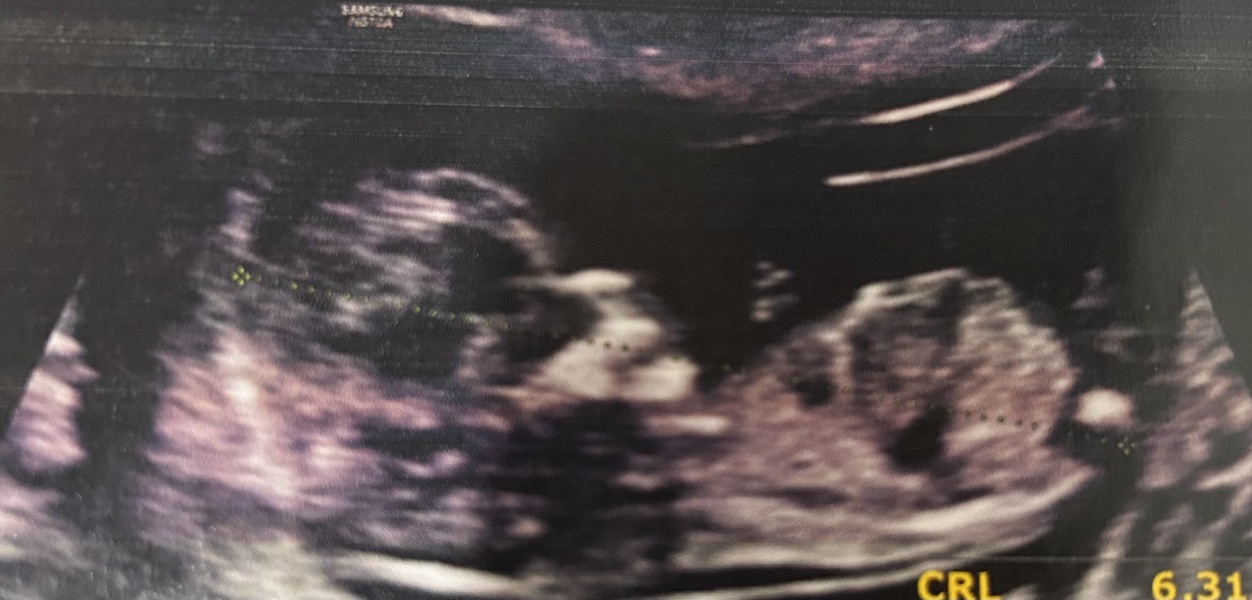

Newmom29 · 16/10/2024 08:57

Hey guys! Can anyone help me finding out the gender.. I’m getting impatient lol

welcome any guesses based on nub theory or skull theory? I’m having a hard time judging. Pls help!